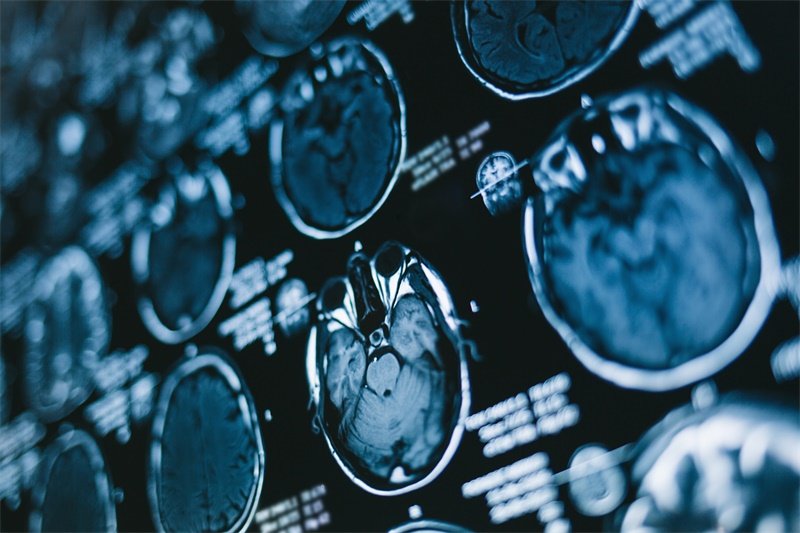

MRI是诊断松果体病变的首选工具,其多平面成像能力可以清晰显示病变与周围结构的关系。增强扫描能帮助判断血脑屏障破坏程度,弥散加权成像(DWI)对鉴别肿瘤性质有特殊价值。对于无法接受MRI检查的患者,CT能快速评估钙化灶和脑室扩张情况。